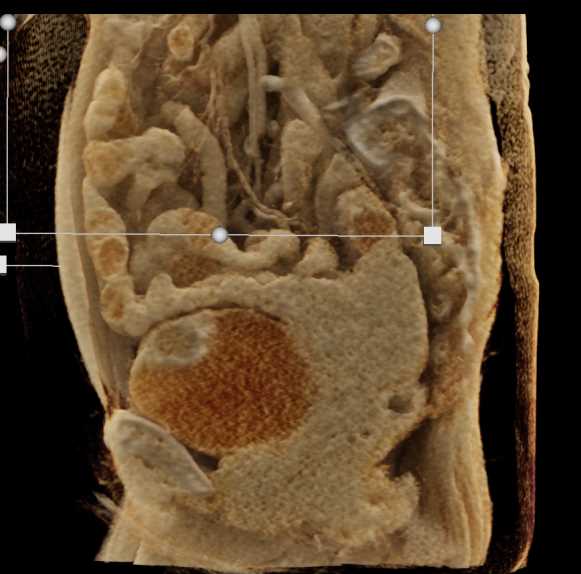

Urachal Carcinoma of the Bladder